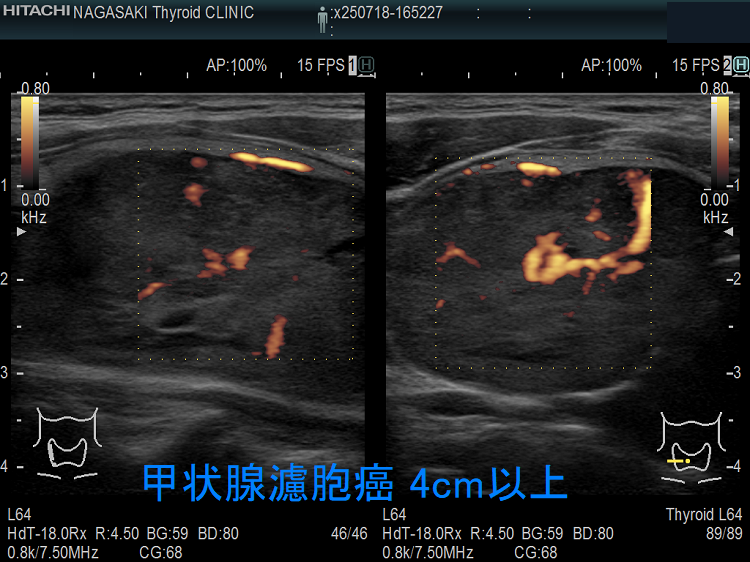

微小浸潤型濾胞癌でも巨大なものは、血管浸潤・遠隔転移します。写真のケースは 4cm以上の微小浸潤型濾胞癌で、切除標本にて血管浸潤を4カ所以上認め、Ki-67 labeling index 7% 高値(>5%)だった(エコーでは内部血流が少なかったのに)。

Ki-67 labeling index >5%は、増殖能が強く予後不良[World J Surg. 2010 Dec;34(12):3015-21.]。